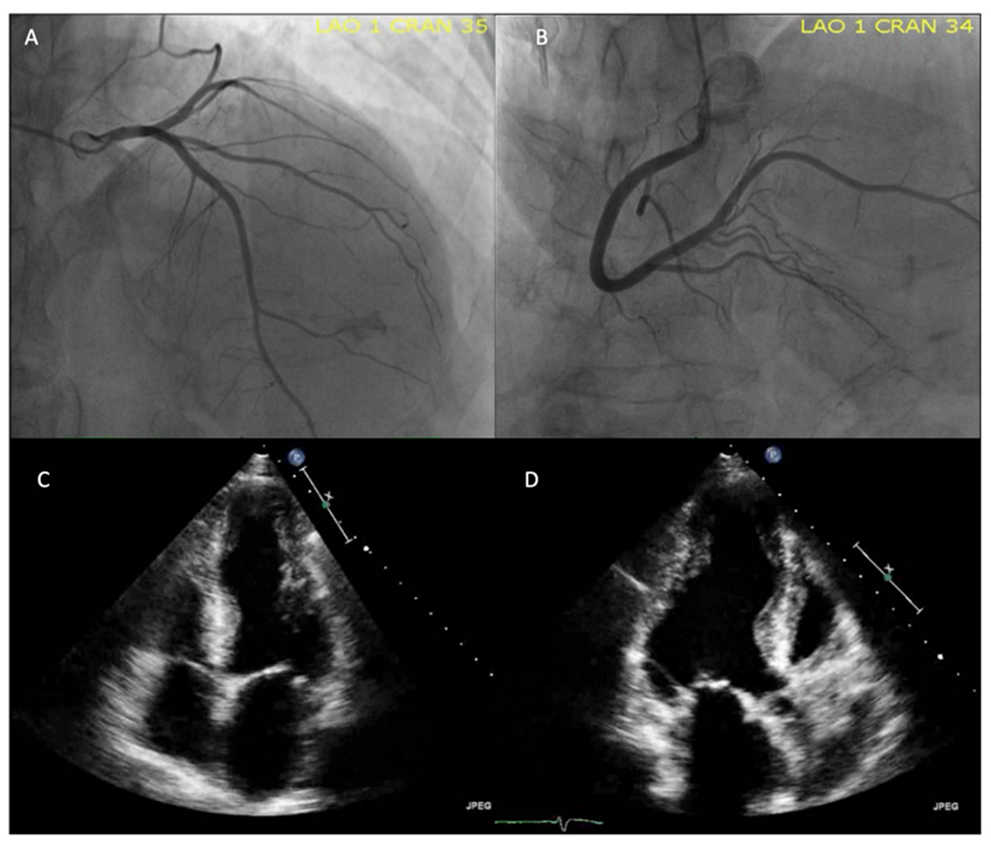

6.3. Echocardiogram

An echocardiogram is the initial and follow-up imaging study in most patients with suspected cardiomyopathy [120]. In the acute phase of Chagas disease, the most frequent finding is pericardial effusion. Mortality in the acute phase is rare (about 1%) and is mainly related to myocarditis [85]. In the above cases, the echocardiographic findings may be motility alterations and LV thickening with significant systolic dysfunction [121].

Nascimento et al. (2013) reported that LV diastolic dysfunction was found in the chronic symptomatic stage of CD, increasing its prevalence as the disease progresses from the phase without systolic dysfunction to the chronic phase with heart failure. Tissue Doppler was the best tool to observe the deterioration of diastolic function, as it is an independent predictor of adverse clinical events [114].

In the early stages (B1 or B2), the echocardiogram may demonstrate alterations of LV segmental mobility ranging from hypokinesia to aneurysm formation [2,121,122]. The cardiac regions frequently affected are the basal segments of the inferior and inferolateral wall and the apex, alterations that cannot be attributed to obstructive coronary artery disease. Segmental LV wall mobility abnormalities identify patients at risk for ventricular arrhythmias and disease progression [121].

The study of segmental mobility alterations is subjective, so the evaluation of deformation by two–dimensional speckle tracking (2DST) can become a useful tool in the early stages by identifying alterations in areas without apparent involvement [5,123]. The use of 2DST is less useful in patients with obvious segmental mobility disorders (Figure 6), but it still serves as a tool to assess the heterogeneity of systolic contraction (mechanical dispersion); these alterations are associated with ventricular arrhythmias independent of LVEF [122,124].

LV apical aneurysms are a pathognomonic finding [98,122] of CCC that may be useful for differential diagnosis with dilated cardiomyopathy (Figure 7). Another frequent presentation site is the inferolateral wall of the LV, although they are not exclusive to these sites [14]. The presence of aneurysms frequently accompanies disease progression to LV systolic dysfunction, where three-dimensional echocardiography and the use of contrast agents offer advantages for their evaluation [122,124]. In advanced stages of the disease, these are characterized by generalized hypokinesia and LV systolic dysfunction, the latter being a predictor of mortality in CCC [124].

The onset of LV diastolic dysfunction can occur early in the disease, even in asymptomatic forms of the chronic stage, with a prevalence of up to 10% [114]. Diastolic and systolic dysfunction coexist in all patients in the advanced stages of the disease. Right ventricular (RV) systolic dysfunction is a marker of poor prognosis.

During dobutamine stress echocardiography, segmental mobility disturbances can be induced in patients with CD without obstructive coronary artery disease [122,124]. Alterations in the microvasculature have been demonstrated to cause perfusion defects in these patients and are believed to be the origin of myocardial damage. The alterations in perfusion occur early in the disease and precede the appearance of alterations in segmental mobility at rest [124].